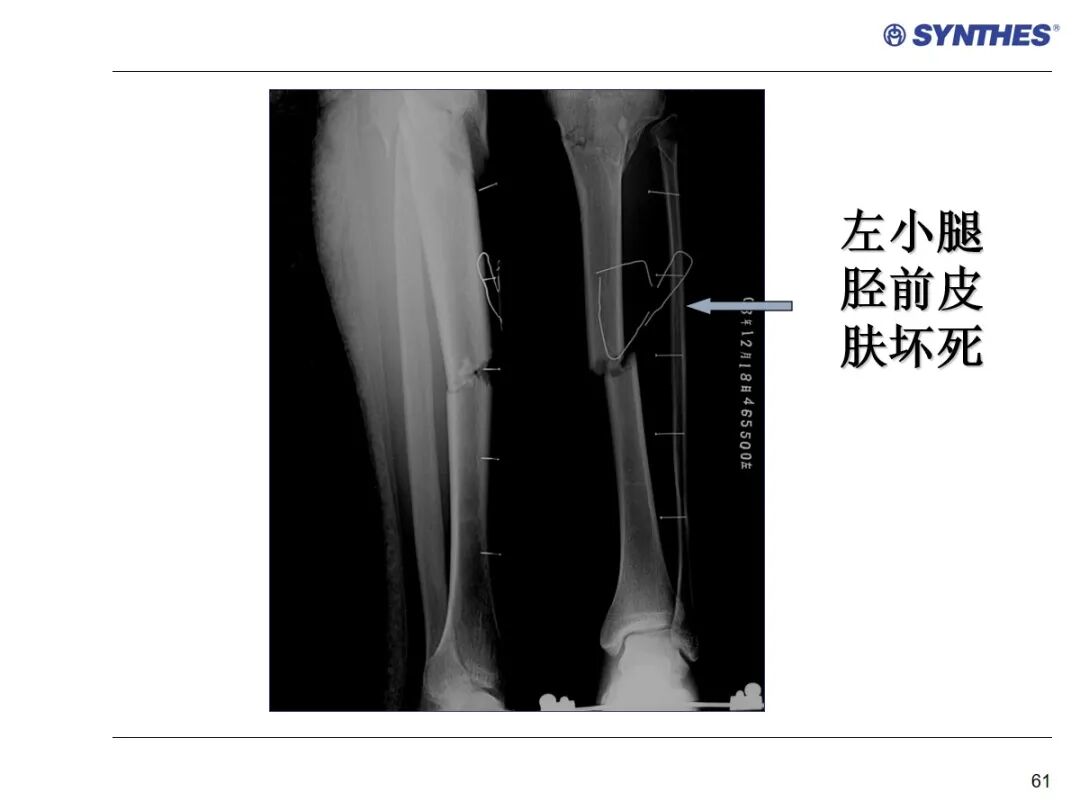

LISS微创固定系统应用技巧,原来如此简单!